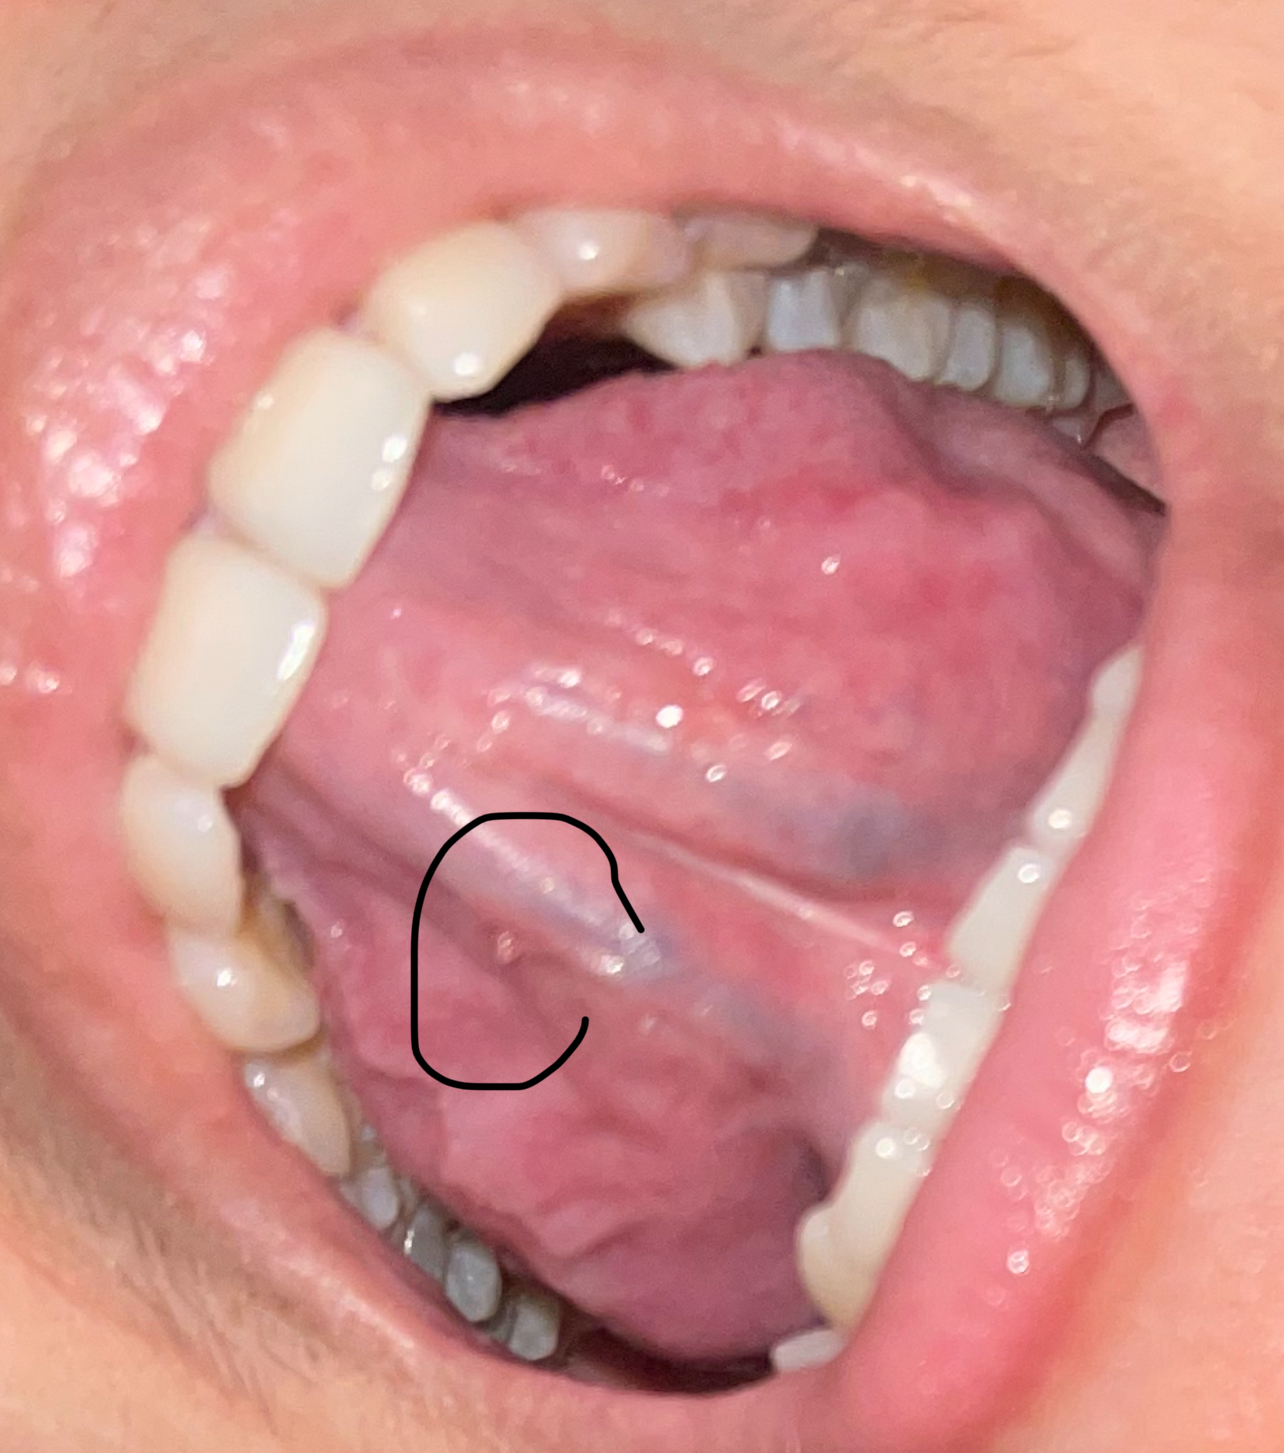

9 เมษายน 2568 17:43:25 #1 https://haamor.com/media/create_topic/20250409174126.jpeg https://haamor.com/media/create_topic/202504091741261.jpeg https://haamor.com/media/create_topic/202504091741262.jpeg https://haamor.com/media/create_topic/202504091741263.jpeg

เป็นติ่งแบบนี้ และมีตุ่มตรงกลาง เป็นอะไรไหมคะ กลัวเป็นหูดหงอนไก่ |

13 เมษายน 2568 10:50:02 #2 จากรูป ไม่ใช่หดูหงอนไก่ครับ ไม่ต้องทำอะไรถ้าไม่โตขึ้น |